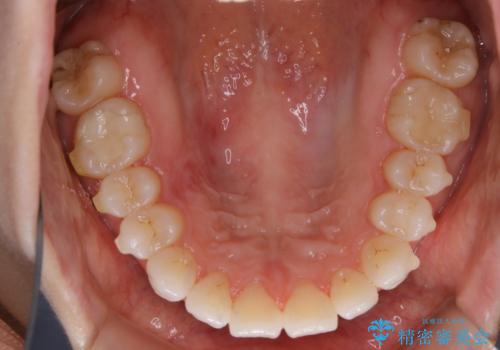

- インビザライン(マウスピース矯正)の治療中にステインが気になり、クリーニング希望とのことでした。

アタッチメントの周囲などに、ステインの付着や、プラークがみられたためPMTC(自費クリーニング)30分コースを行いました。

インビザラインで矯正治療中に、クリーニングを行ったbeforeafter写真です。